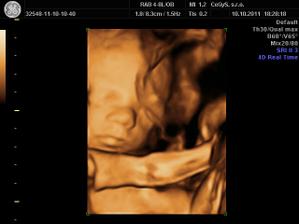

10.10 - 3D u Dr. Hlavacika v CeGys, vysoka spokojnost, mily pristup, krasne fotecky, sme na nasu Misku hrdi - je krasna uz teraz!!! V 25tt vazi o trosku viac ako by mala a to 725g...